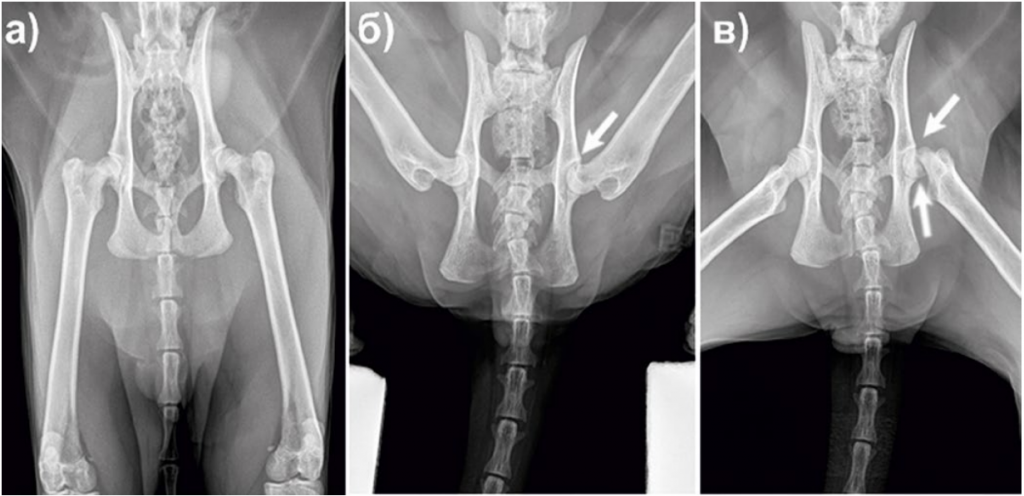

Перелом бедра у кошки

Перелом бедра у кошки 139 фотографий